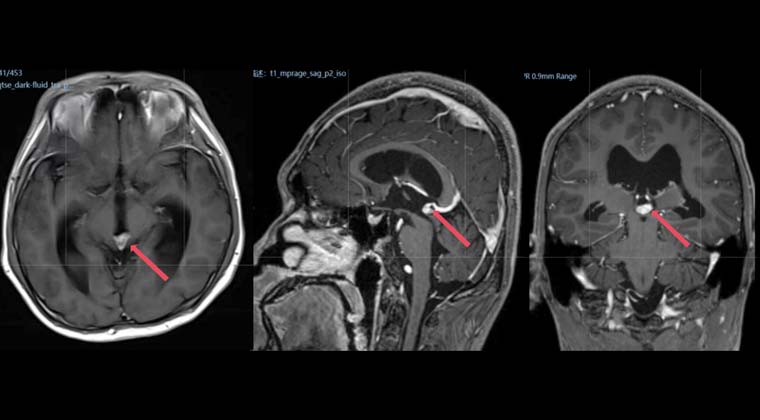

Пациент - мужчина, 49 лет

Диффузная крупноклеточная B-клеточная лимфома

002021 до начала лучевой терапии выполнено обычное и контрастное МРТ головы:

Образование в мозолистом теле, распространяющееся на теменную долю, соответствует лимфоме.

102021 проведена радиотерапия очага в головном мозге с использованием 6MV-X лучей, с одновременным интегрированным бустом: PTV1: 40 Гр / 2 Гр / 20 сеансов; PTV2: 36 Гр / 1,8 Гр / 20 сеансов; 5 сеансов в неделю

Повторное МРТ 002021 показало изменения после лечения лимфомы, очаги в черепе уменьшились по сравнению с предыдущими исследованиями.

До лечения:

После лечения: